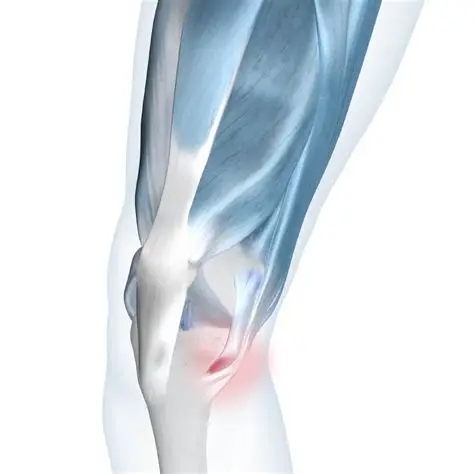

Chondromalacia Patella

Knee Bursitis

Anterior Cruciate Ligament Tear

Medial Collateral Ligament Injury

Lateral Collateral Ligament Injury

Posterior Cruciate Ligament Injury

Patellar Tendonitis

Knee Fracture

Knee Osteoarthritis